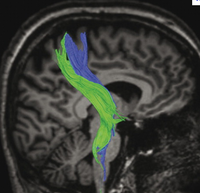

Tractus Cortico-Spinalis AKA Pyramidebaner

De blå baner er fra den præcentrale region, de grønne fra den postcentrale region

Bemærk forløbet af tractus Cortico-Spinalis på den sagitale billede. Bemærk det S-formede forløb hvor forløbet fra Cortex mod Pons har retning mod den posteriore del af fossa cranii anterior. Det er vigtigt at holde sig dette for øje ved kirurgi i området umiddelbart foran gyrus præcentralis.